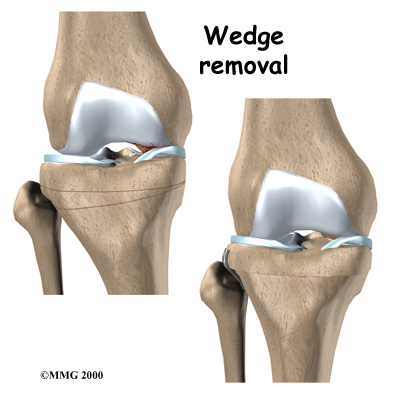

Proximal Tibial Osteotomy

OA usually affects the side of the knee closest to the other knee (called the medial compartment) more often than the outside part (the lateral compartment). OA in the medial compartment can lead to bowing of the knee. As mentioned earlier, a bowlegged posture places more pressure than normal on the medial compartment. The added pressure leads to more pain and faster degeneration where the cartilage is being squeezed together.

Surgery to realign the angles in the lower leg can help shift pressure to the other, healthier side of the knee. The goal is to reduce the pain and delay further degeneration of the medial compartment.

One procedure to realign the angles of the lower leg is called a proximal tibial osteotomy. In this procedure, the upper (proximal) part of the shinbone (tibia) is cut, and the angle of the joint is changed. This converts the extremity from being bowlegged to straight or slightly knock-kneed. By correcting the joint deformity, pressure is taken off the cartilage. A proper joint angle actually allows the cartilage to regrow, a process called regeneration.

This surgical procedure is not always successful. Generally, it will reduce your pain but not eliminate it altogether. The advantage to this approach is that very active people still have their own knee joint, and once the bone heals there are no restrictions on activities.

A proximal tibial osteotomy in the best of circumstances is probably only temporary. It is thought that this operation buys some time before a total knee replacement becomes necessary. The benefits of the operation usually last for five to seven years if successful.